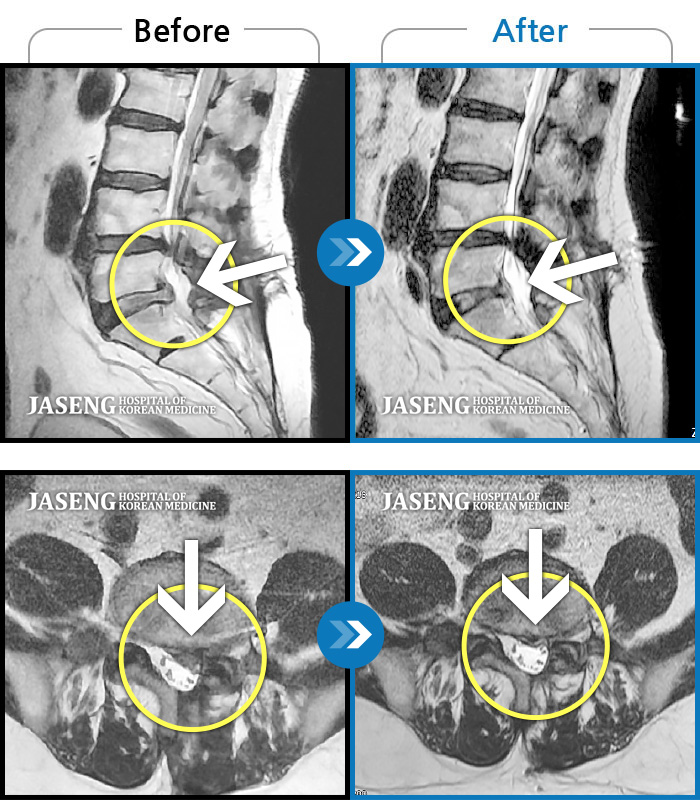

컴퓨터 모니터로 많이 튀어나온 디스크도 쑥 들어간 mri사진 사례들을 여러개 보여주시며 이보다 더 많은 사례가 있다고 제게 희망을 주셨습니다